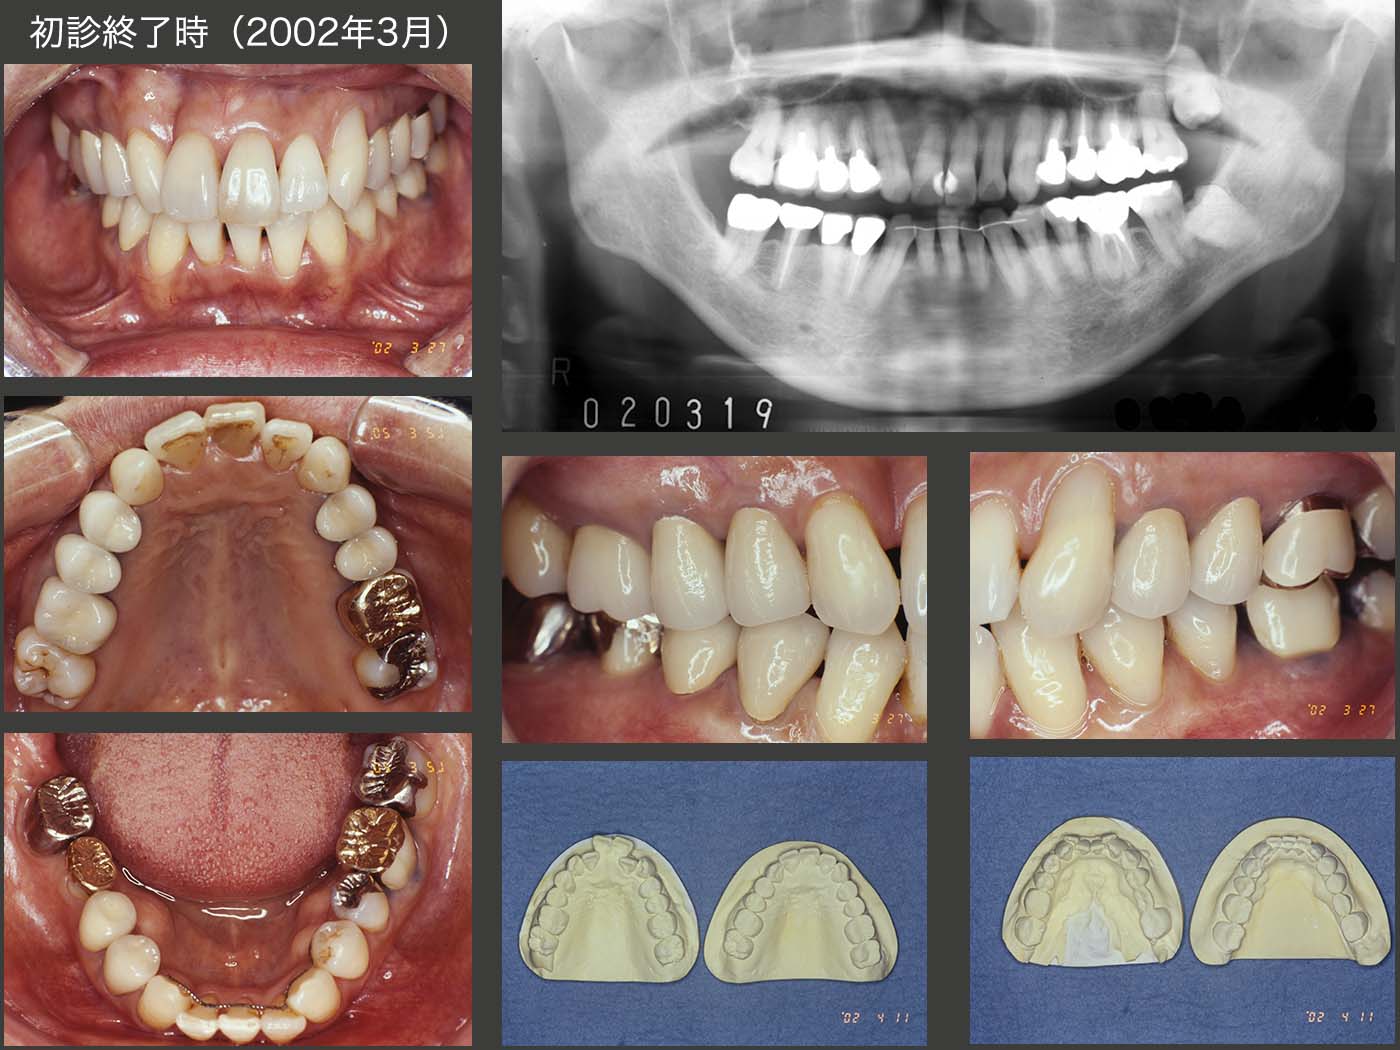

16.左上8を左下6に移植後、置換性吸収が生じた症例

2000年2月初診,54歳女性.主訴は,色々治したい.主訴の一つである上下顎前歯の審美性の改善について,セット・アップ模型を用い治療後の形態を提示した.前歯部を内側に入れるためのスペース確保のために,抜去する歯を上下それぞれ最小限の1本にしたい.また,臼歯部の咬合は変化させないという治療方針をたてた.しかし,歯列の正中がずれる欠点があることを説明したところ,患者さんはこの方針での治療を希望された.なお歯周ポケットは,右下7の遠心が7mm以外,特に問題はなかった.

2019年3月の状態.移植された右下6は,ドナー歯が上顎側切歯であり,隣在歯と連結固定しなかったにもかかわらず,約19年間経過は良好である.一方,移植後約17年経過の左下6については,残念ながら置換性吸収が進行している.もうこのまま経過を観察するしか術がない.